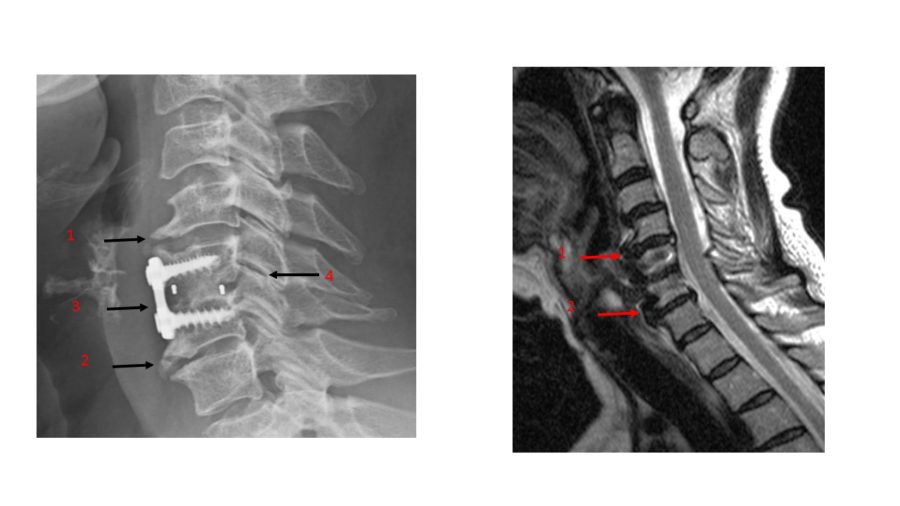

Neck Surgery and Its Consequences: Adjacent Segment Disease

Nackenoperation und ihre Folgen: Anschlusssegmenterkrankung

In der Centeno-Schultz-Klinik haben wir uns dazu verpflichtet, jedem Patienten die fortschrittlichste nicht-chirurgische Behandlung für häufige orthopädische Erkrankungen zu bieten, wobei wir Injektionen mit Thrombozyten, Zytokinen und Stammzellen einsetzen. Die mit einer Operation verbundenen Risiken sind zahlreich und wurden in früheren Blogs besprochen. Dazu zählen: Infektion, Versagen, anhaltender oder erhöhter Schmerz, eine Veränderung der Biomechanik … Continued